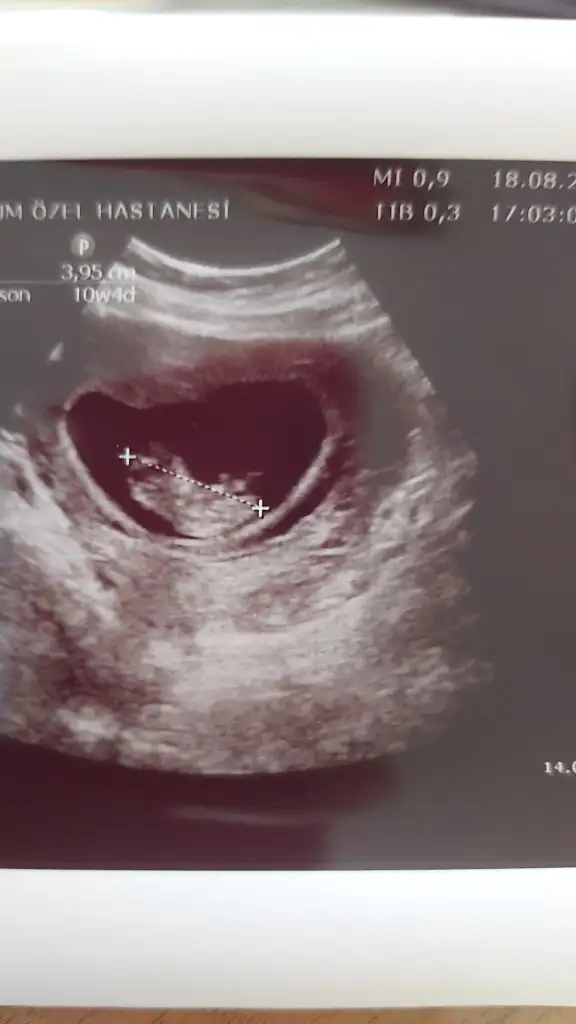

Erkek ve kız için 11 + 12+ yada 13 hafta usg görüntüsü olmalı açıklamalar asagıda yazıyorrabbim herkesin gönlüne göre nasip etsin inşallah .. ecmain

[/B]Eki Görüntüle 473828 gordugunuz gibi ust taraftaki simgedende anlasildigi gibi eger cikinti paralel ise kiz

yok 30°lik bir aciyla yukari dogru bakiyorsa %99 oglunuz olacak demektir simdi bi kac ornek resimler daha koyacagim kiziminkide dahil

Eki Görüntüle 473831 simdi burada cikintilara bakin eger bel popo cizgisine paralel ise kiz

yok 30 derecelik bir aciyla yukari bakiyorsa erkek

hani dr lar 12. 13. haftalarda belli degil ama

kemik yapisina gore kiz gibi

yahut erkege benziyor diyorlar ya

iste o nub teorisi kizlar dr buradan yola cikiyor